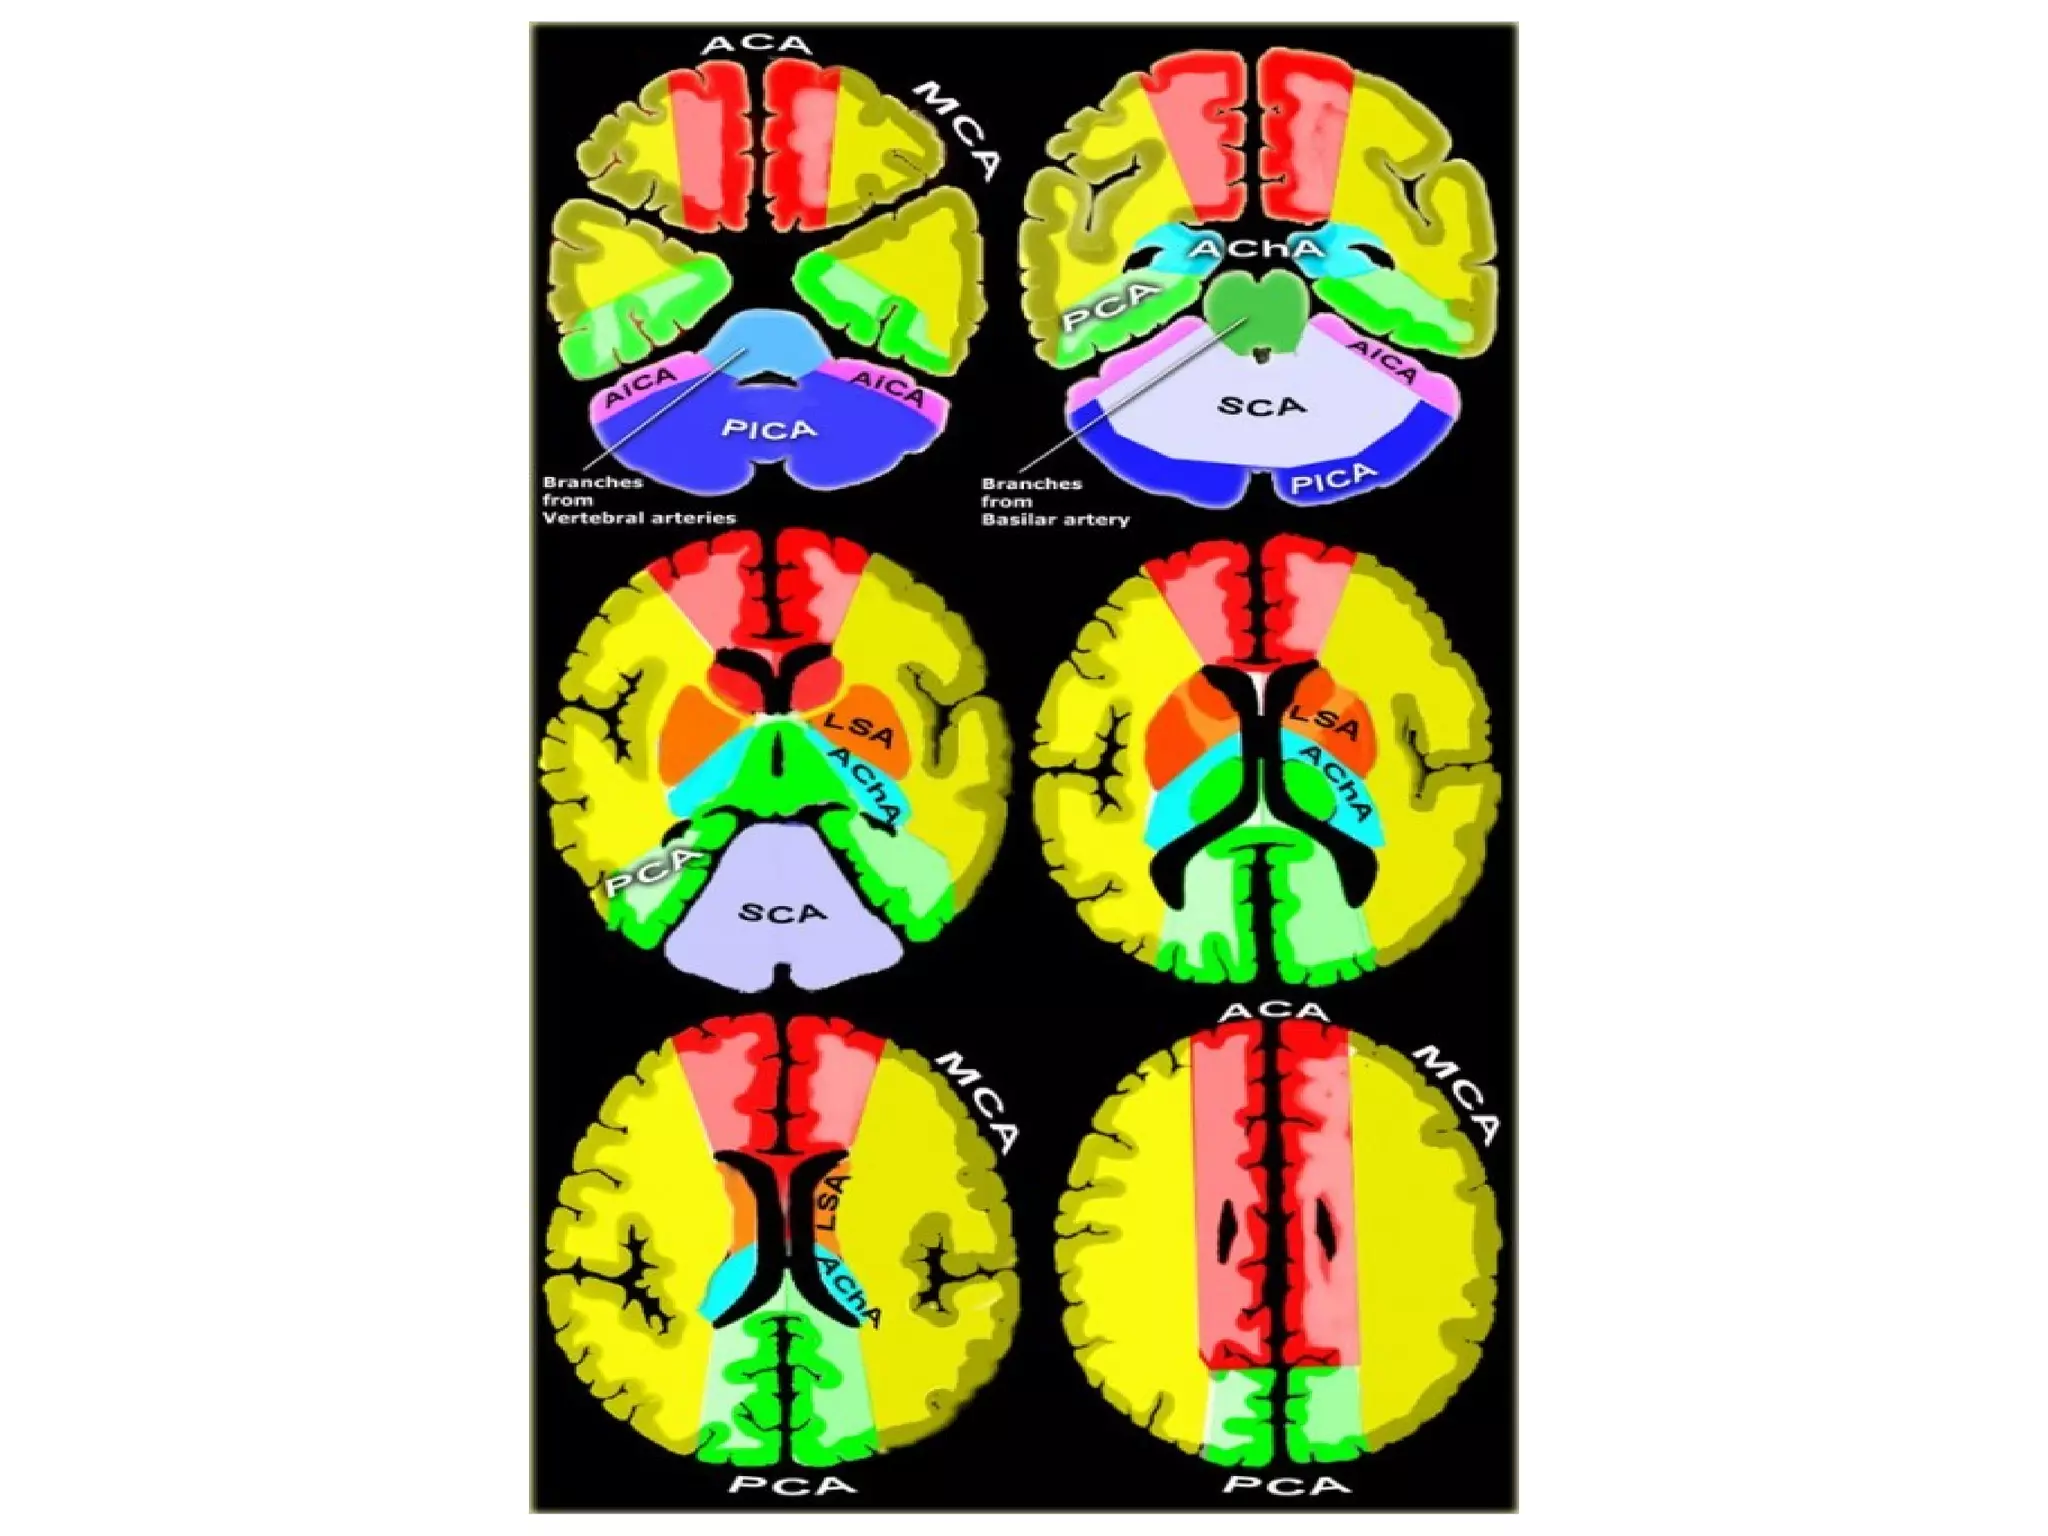

b) Cerebral Arterial Territory :

1-Posterior Inferior Cerebellar Artery

2-Superior Cerebellar Artery

3-Branches from vertebral and basilar artery

4-Anterior Choroidal artery

5-Lenticulostriate arteries

6-Anterior cerebral artery

7-Middle cerebral artery

8-Posterior cerebral artery

1-Posterior Inferior Cerebellar Artery (PICA in blue)

-The PICA territory is on the inferior occipital

surface of the cerebellum and is in equilibrium

with the territory of the AICA in purple which

is on the lateral side

-The larger the PICA territory , the smaller the

AICA and vice versa

2-Superior Cerebellar Artery (SCA in grey)

-The SCA territory is in the superior and tentorial

surface of the cerebellum

-These branches supply the medulla oblongata

(in blue) and the pons (in green)

4-Anterior Choroidal artery (AchA in blue)

-The AChA originates from the posterior wall of

the ICA between origin of PCOM which is 2-5 mm

proximally and the internal carotid termination,

which is 2-5 mm distal to the AChA

The territory of the AChA is part of the hippocampus ,

the posterior limb of the internal capsule , optic tract

, mid brain , lateral geniculate nucleus and choroid

plexus of the anterior part of the temporal horns of

the lateral ventricles

-It has 2 segments , cisternal and intraventricular

-The lateral LSA (in orange) are deep penetrating

arteries of the middle cerebral artery (MCA)

-Their territory includes most of the basal ganglia

-The medial LSA (indicated in dark red) arise from

the ACA (usually the A1 segment)

-Heubner's artery is the largest of the medial

lenticulostriate arteries and supplies the

anteromedial part of the head of the caudate and

anteroinferior internal capsule

-The territory of the lateral lenticulostriate

perforating arteries of the MCA is indicated

with a different color from the rest of the

territory of the MCA because it is a well-

defined area supplied by penetrating branches

which may be involved or spared in infarcts

separately from the main cortical territory of

the MCA

6-Anterior Cerebral Artery (ACA in red)

-The ACA supplies the medial part of the frontal

and the parietal lobe and the anterior portion

of the corpus callosum , basal ganglia and

internal capsule

7-Middle cerebral artery (MCA in yellow)

-The cortical branches of the MCA supply the

lateral surface of the hemisphere except for

the medial part of the frontal and the parietal

lobe (anterior cerebral artery) and the inferior

part of the temporal lobe (PCA)

8-Posterior cerebral artery (PCA in green)

-P1 extends from origin of the PCA to the posterior

communicating artery contributing to the circle

of Willis

-Posterior thalamoperforating arteries branch off

the P1 segment and supply blood to the midbrain

and thalamus

-Cortical branches of the PCA supply the

inferomedial part of the temporal lobe , occipital

pole , visual cortex and splenium of the corpus

callosum